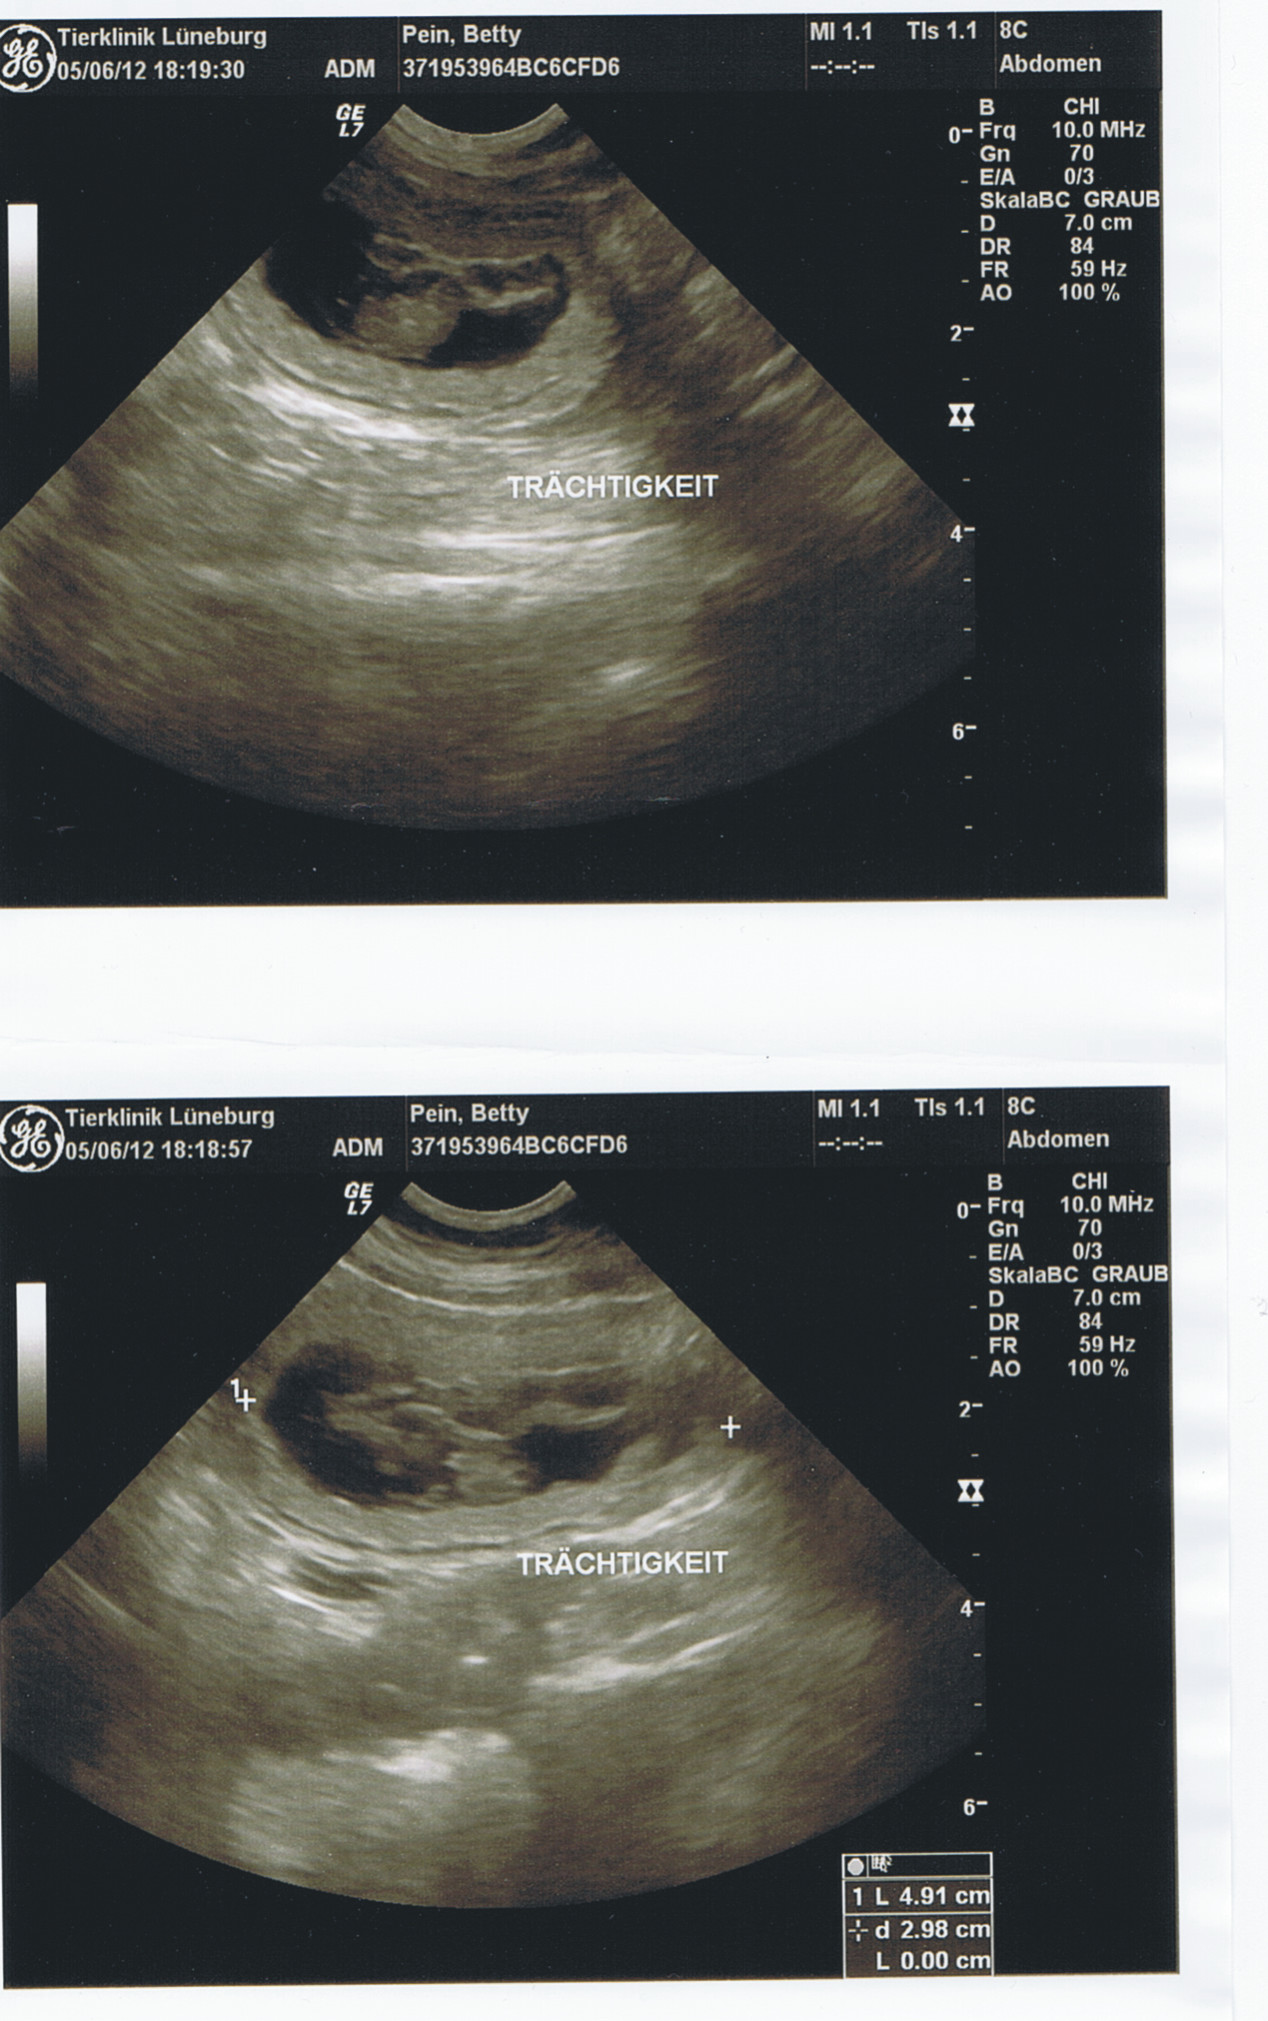

05.06.12

Tag 27. der Trächtigkeit

Es besteht kein Zweifel, Betty erwartet Welpen von Rasmus. Wir freuen

uns riesig.

Es ist nicht zu glauben wie die Zeit vergeht. Erst warteten wir

gespannt auf die Läufigkeit unserer Knutschkugel, dann war es soweit.

Hoffentlich klappt alles beim Decken. Und wieder hieß es warten, dann

war es soweit der Termin in der Klinik zum Ultraschall, hurra hurra

Betty und Rasmus werden Eltern. Und nun sind die Mini´s 4 Wochen , und